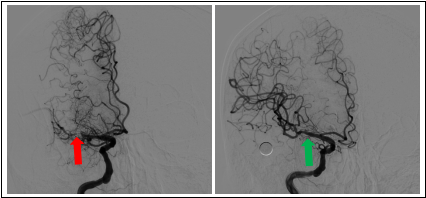

基底动脉闭塞患者接受机械取栓治疗前后对比图

右侧大脑中动脉慢性闭塞再通前后对比图